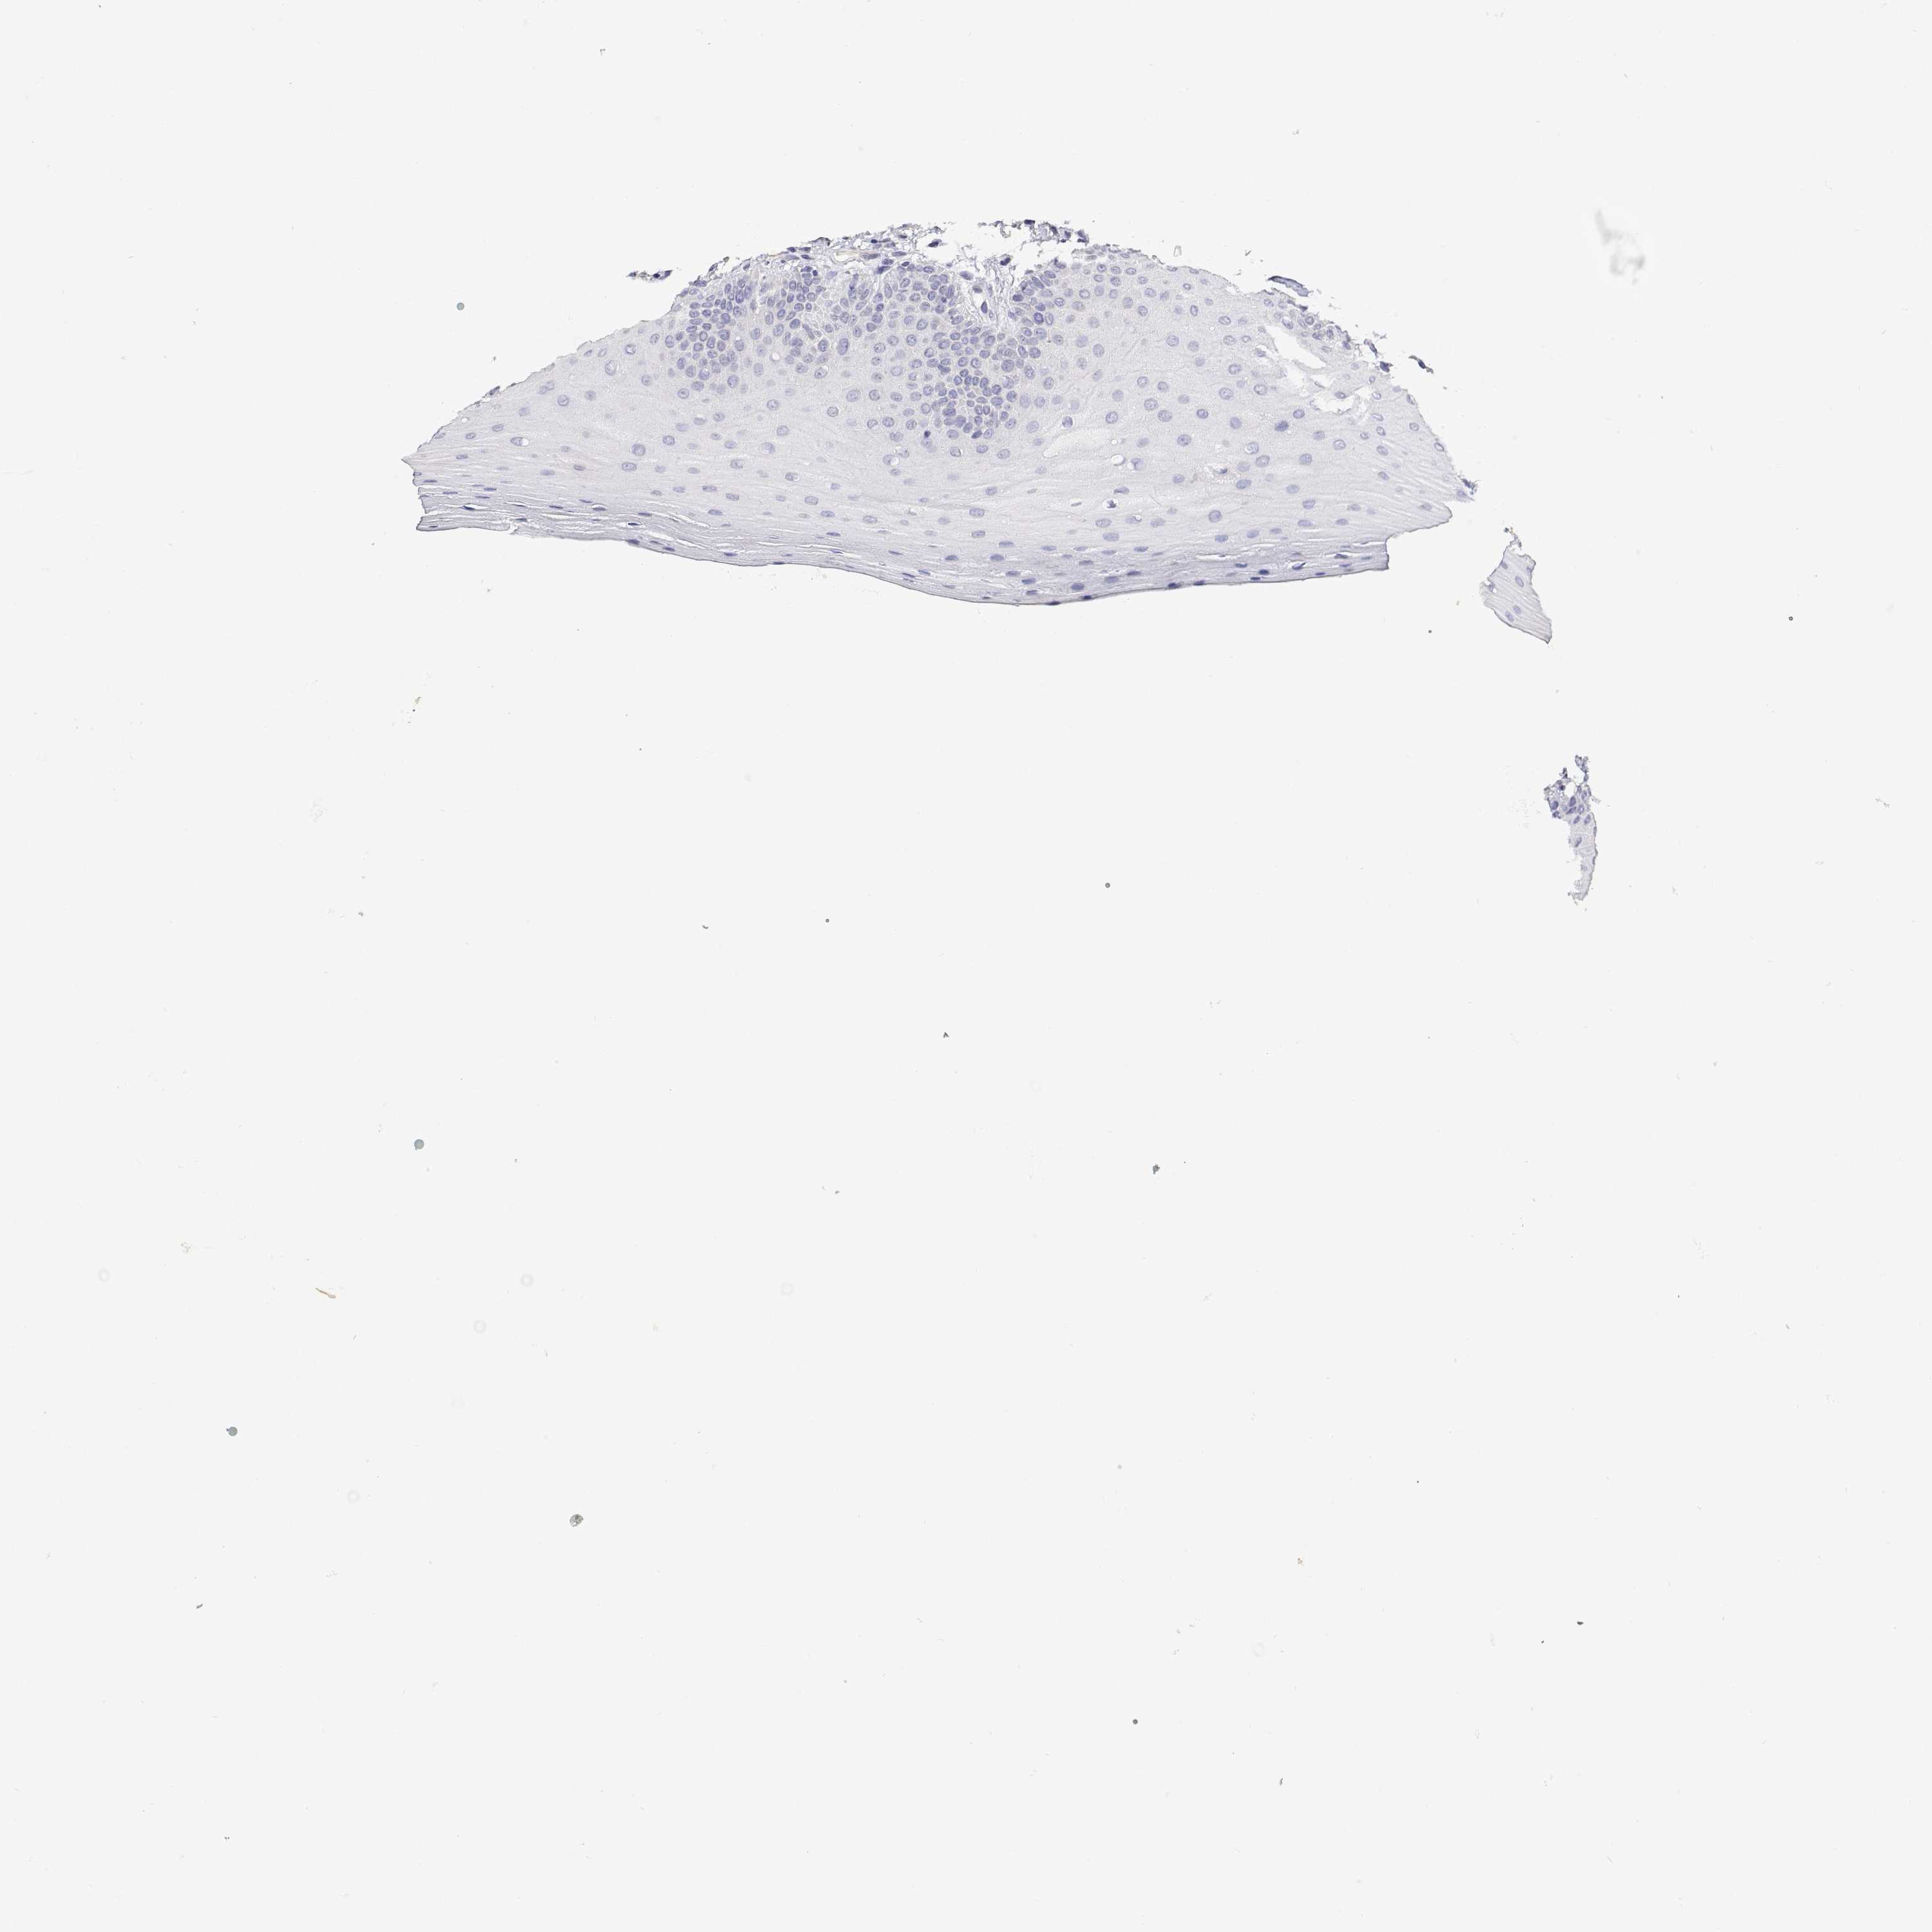

PLCB1